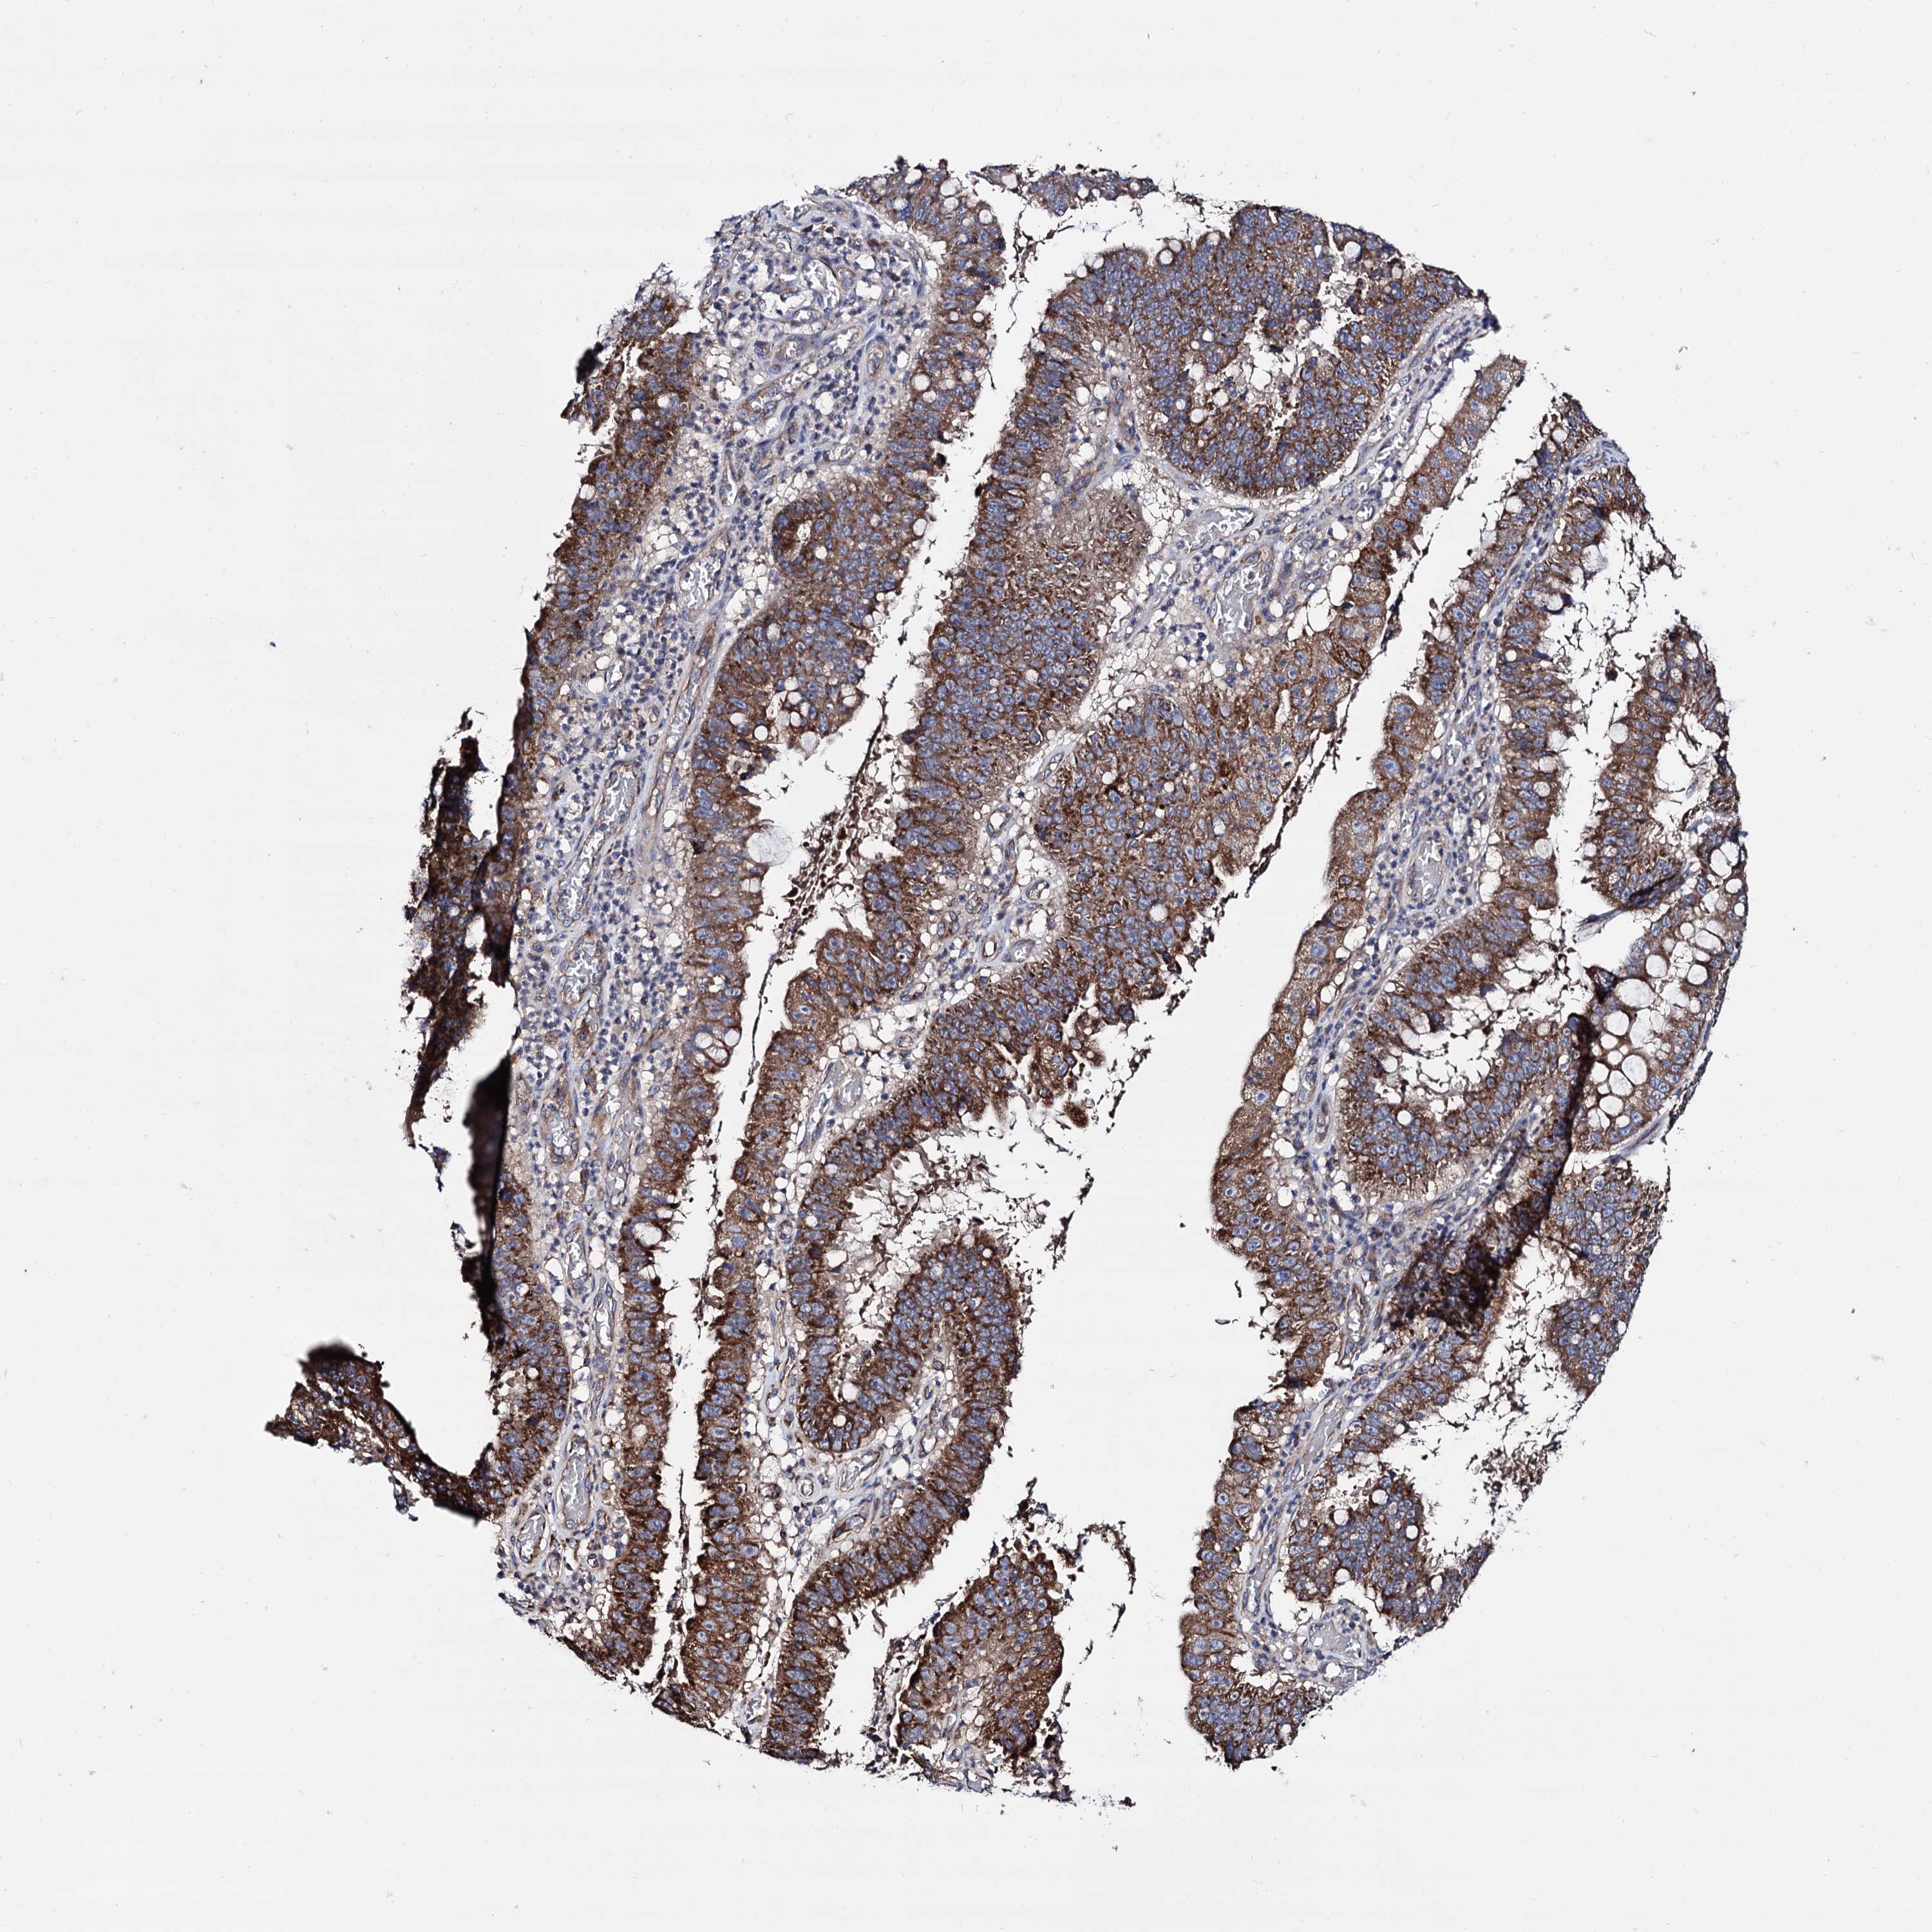

STOMACH CANCER - Protein expressioni

A mouse-over function shows sample information and annotation data. Click on an image to view it in a full screen mode. Samples can be filtered based on level of antibody staining by selecting one or several of the following categories: high, medium, low and not detected. The assay and annotation is described here.

Note that samples used for immunohistochemistry by the Human Protein Atlas do not correspond to samples in the TCGA dataset.

Antibody stainingi

Antibody staining in the annotated cell types in the current human tissue is reported as not detected, low, medium, or high, based on conventional immunohistochemistry profiling in selected tissues. This score is based on the combination of the staining intensity and fraction of stained cells.

Each image is clickable and will lead to virtual microscopy that enables deeper exploration of all samples and also displays staining intensity scores, fraction scores and subcellular localization as well as patient and tissue information for each sample.

Antibody HPA040845

Staining

High

Intensity

Strong

Quantity

>75%

Location

Nuclear

Adenocarcinoma, NOS

Adenocarcinoma, High grade